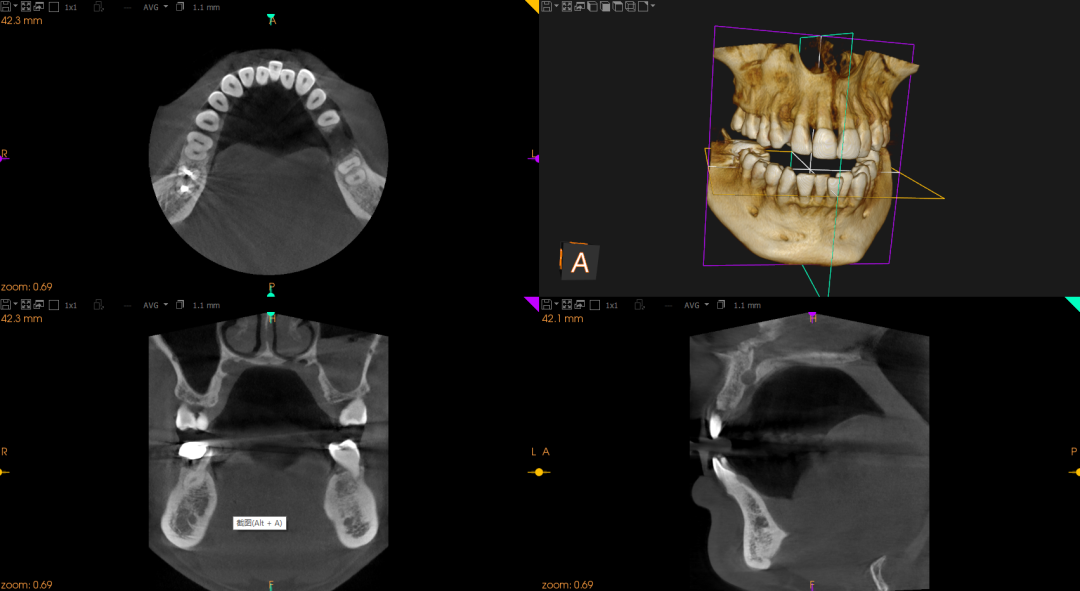

全新设备—美国锐珂口腔全景CT

我院最新引进美国锐珂口腔全景CT一台,已正式投入使用。三大功能可全面满足口腔科各种需求,提供更为准确的多层面三维图像。能大大提高口腔疾病预防效率,患者得以享受数字口腔高科技、高时效、高精确度的服务,促进人们口腔健康质量的提升。该设备对我院的临床诊疗水平将如虎添翼,也标志着我院口腔医疗在科技口腔、数字口腔的道路上又跨出了飞跃性的一步!

口腔CT:口腔疾病的全面检查及种植牙的测量;

口腔全景:三维立体成像无重叠,无伪影全面展示口腔影像;

头影测量:可绘制七种不同的头影测量二维数据并出具七种不同的测量值报告,全面满足正畸需求。